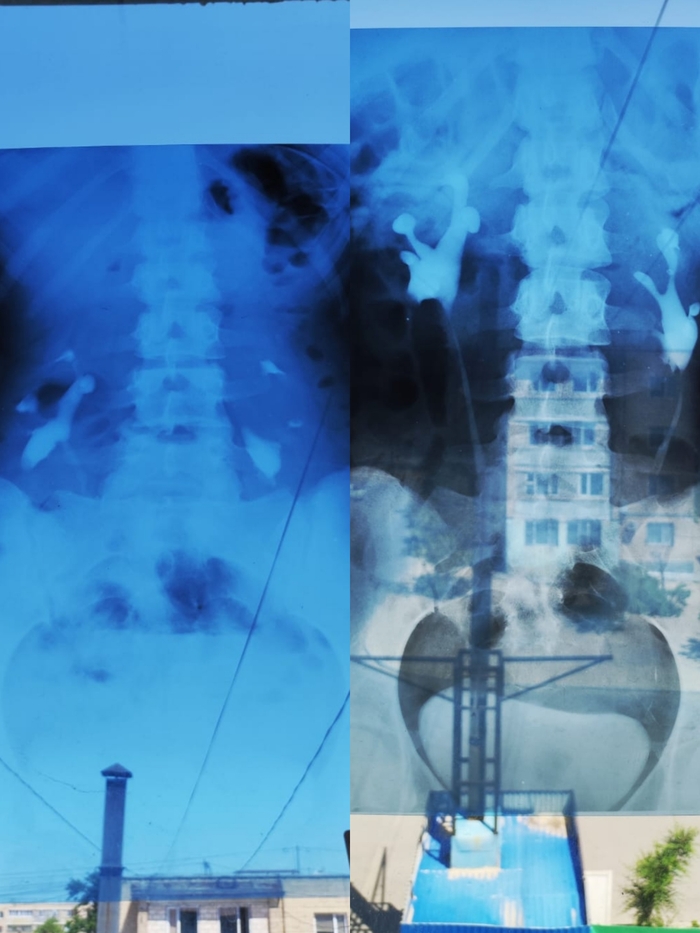

Снимки экскреторной урографии стоя и лежа: видно, насколько опускаются почки при смене положения (фотки на окне, иначе как подсветить рентген))